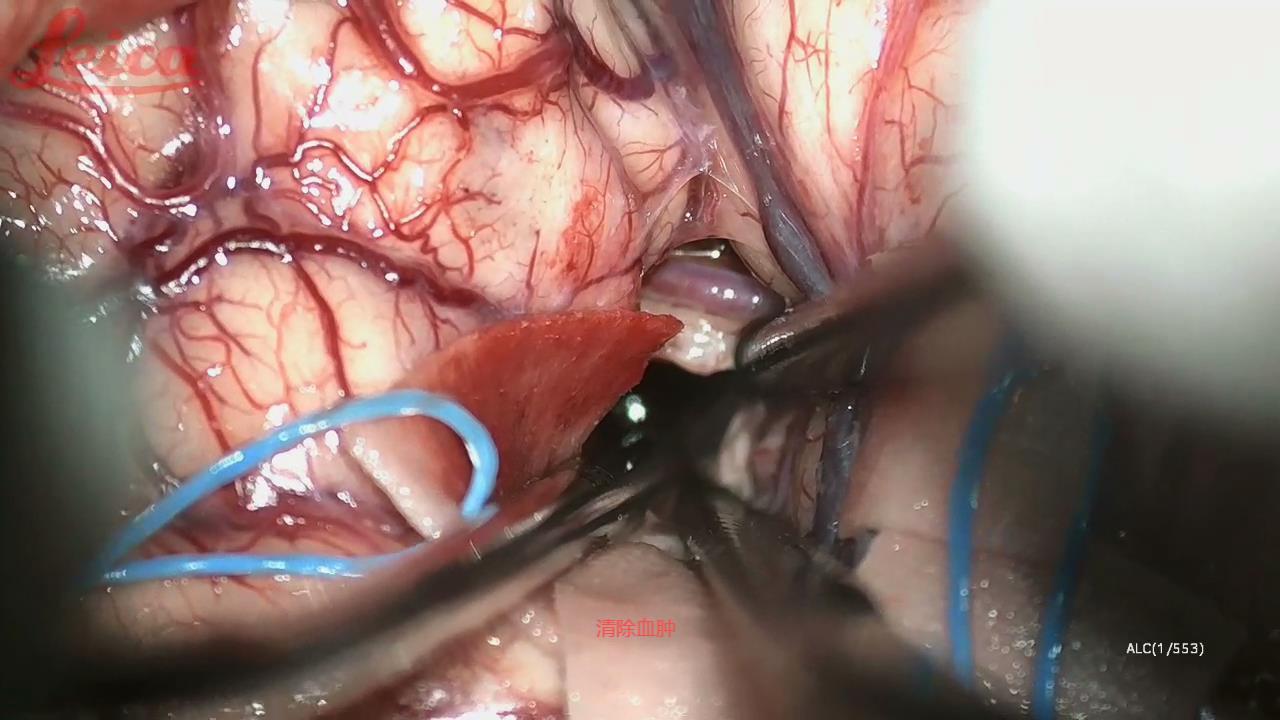

经外侧裂-岛叶造瘘清除血肿简要

经外侧裂-岛叶造瘘清除基底节出血